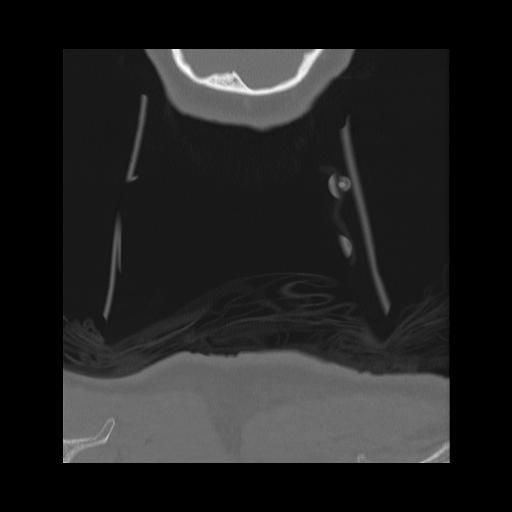

16 HUESO,,Coronal,2.000,HUESO,Coronal,